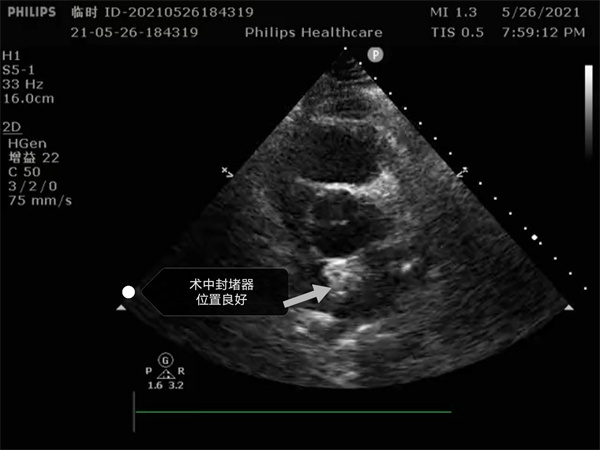

尤其是患者是個三房心,正常的人是有二個心房,這是一種少見的先天性心臟畸形, 如何在三房心把這個洞堵住,而且不影響心臟正常結構,是這個手術難點。沈主任組織全科進行術前討論,5月26日下午5點開始手術,導絲如何在不規則的只有米粒大小的卵圓孔里通過,鞘管如何通過,如何進入卵圓孔連接的副房,避免封堵器夾住隔膜,這些難點在術中被沈主任團隊一一化解,手術歷時二小時,隨著封堵器成功釋放,導管室外響起來熱烈的掌聲。

就這樣三房心合并卵圓孔未閉發生過三次腦梗的患者,在安康市中心醫院心內科導管室成功進行了國內第二例介入封堵手術。